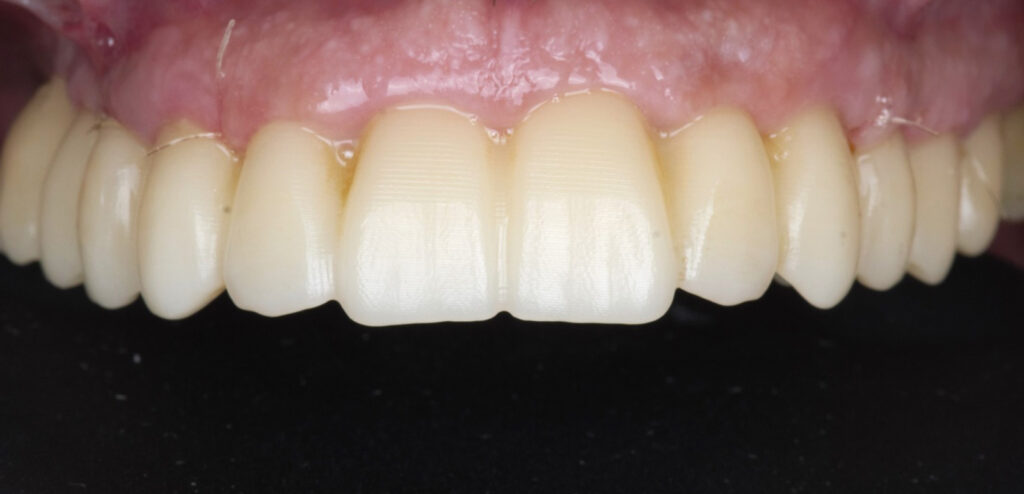

Caso clínico, Dr. José Amador Cabezas

Carga inmediata maxilar con cirugía guiada, registro fotogramétrico y provisionalización inmediata.

En este caso, el Dr. José Amador Cabezas aborda la rehabilitación completa de un maxilar superior comprometido por enfermedad periodontal avanzada, lesiones periapicales y múltiples restauraciones fallidas.

Tras la planificación protésicamente guiada y la colocación de implantes mediante cirugía guiada, se realizó el registro fotogramétrico con T-Marker sobre los Multi-Unit para capturar con precisión la posición real de los implantes y asegurar la pasividad de la estructura provisional.

Gracias a este flujo, el paciente pudo salir de la consulta con una prótesis fija inmediata el mismo día de la cirugía, iniciando así un proceso restaurador más preciso, más predecible y completamente integrado en el entorno digital.

La combinación de cirugía guiada, fotogrametría y carga inmediata permite un control preciso de la posición implantaria y una correcta pasividad protésica desde el primer día.